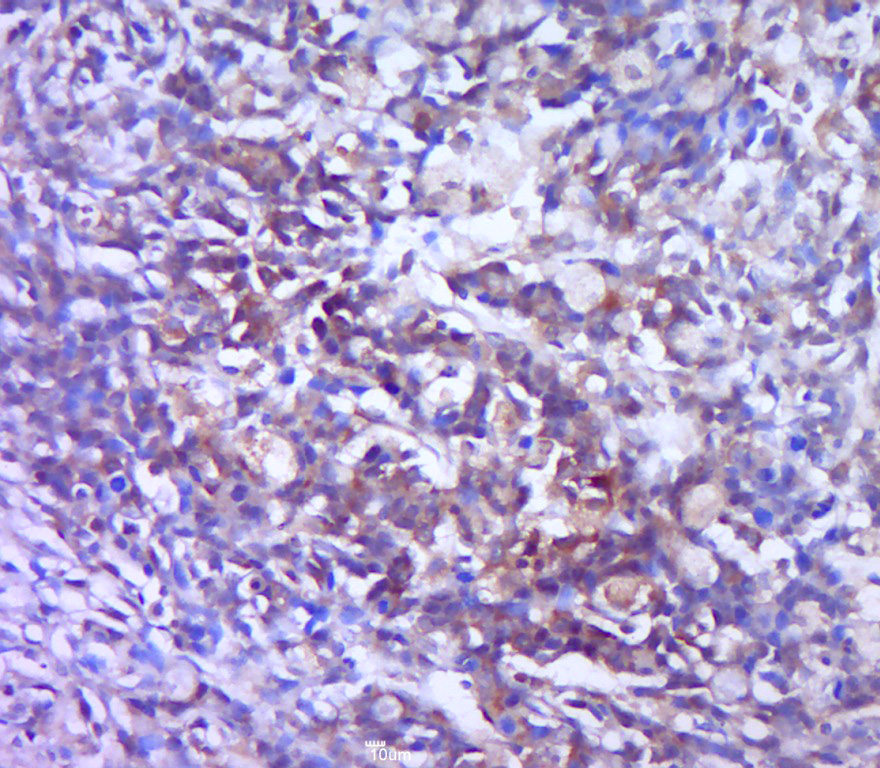

Paraformaldehyde-fixed, paraffin embedded (human gastric carcinoma); Antigen retrieval by boiling in sodium citrate buffer (pH6.0) for 15min; Block endogenous peroxidase by 3% hydrogen peroxide for 20 minutes; Blocking buffer (normal goat serum) at 37°C for 30min; Antibody incubation with (Galectin 3) Polyclonal Antibody, Unconjugated (bs-20700R) at 1:400 overnight at 4°C, followed by a conjugated secondary (sp-0023) for 20 minutes and DAB staining.